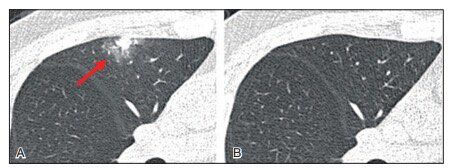

▲图3 A.CT平扫发现右上肺叶部分显示毛玻璃样密度结节,直径测量约17.64 mm,初步诊断为细支气管肺泡癌(BAC)可能,建议3个月随访观察。B.3个月后CT扫描图像显示GGN消失,证实为局灶性非特异性炎症